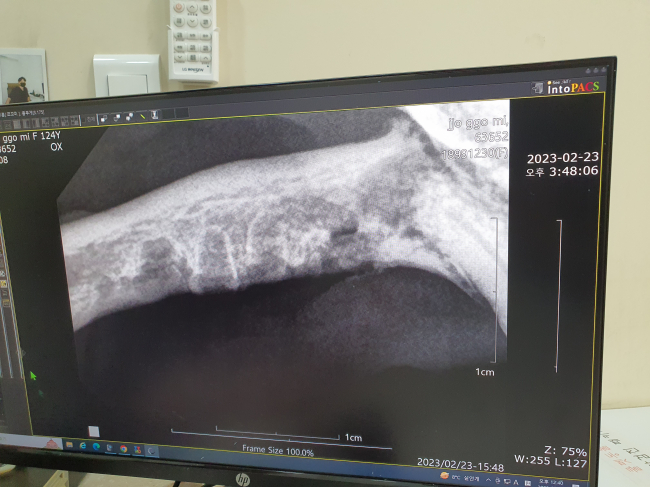

| 치료과정 | 쪼꼬미는 23년 2월 20일 구조,협회 문의 후 2월 23일 구내염 수술을 하기위해 병원에 입원 하였습니다.진료시 의사선생님께서 그냥 보아도 염증이 상당히 진행된 아주 심한 경우라고 하셨습니다. 사납지 않고 온순한 성격으로 마취를 하지않은 상태로 진료를 보는 것은 어렵지 않았습니다. 수술 하기 전 건강검진을 진행하였고 그 결과 구내염 또는 복막염으로 인한 염증 수치는 높았으나 수술에는 문제 없다하여 당일 발치 수술을 하게 되었습니다.쪼꼬미는 진료시 송곳니 제외 전발치를 하기로 하였는데,마취 후 수술 도중 송곳니와 윗 잇몸 상태가 너무 심각하다며 송곳니도 뽑아야 한다는 연락을 중간에 받았고,저는 그 부분에 동의 하였습니다.수술이 끝나고 난 후 통증이 심할거라하여 1일간 입원 시킨 후 상태 회복을 위해 진통제와 수액을 투여하며 안정을 취하였고,습식으로 된 환자식에 항생제 및 약을 섞어 퇴원시까지 복용하였습니다.약은 12시간 간격으로 아침 저녁 2주 복용, 그 후 하루에 1번씩만 복용하라는 안내 받고 2월24일 퇴원,현재 3월27일 처방받은 약은 복용을 다 마친 상태입니다.퇴원하고 일주일은 침이 많이 나왔는데 지금은 많이 줄어들어 건사료도 먹으려고 해 상태가 많이 좋아진 것 같습니다. |